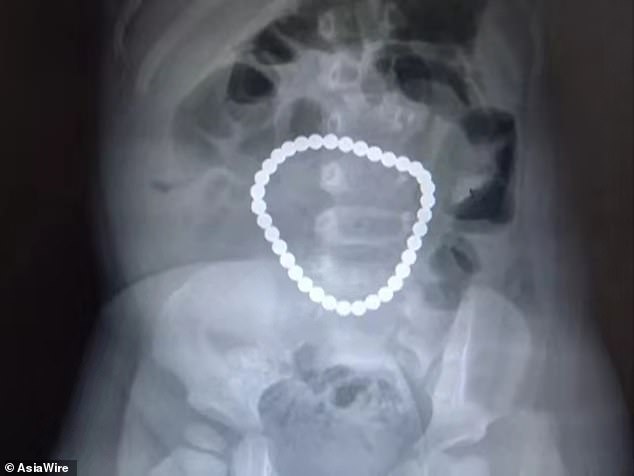

ក្រោយស្កេនម្ដងទៀត វេជ្ជបណ្ឌិតបញ្ជាក់ថា មានគ្រាប់ខ្សែដៃ ៣៦គ្រាប់ នៅក្នុងពោះវៀន ដោយគ្រាប់ទាំងនេះ បានភ្ជាប់ជាមួយគ្នា។ ខ្សែដៃ ៣៦គ្រាប់នេះ បានបង្កថ្នក់ ២នៅក្នុងពោះវៀន ហើយអាចបណ្ដាលឲ្យលេចចេញសារធាតុរាវ ចេញពីពោះវៀន។

បន្ទាប់មក វេជ្ជបណ្ឌិត បានវះកាត់យកគ្រាប់ខ្សែដៃទាំង ៣៦គ្រាប់ ចេញពីពោះទារក ដោយចំណាយពេល ១ម៉ោង។ ពេលនេះ ទារកបានធូរស្រាលហើយ ដោយកំពុងបន្ដសម្រាកនៅមន្ទីរពេទ្យ។